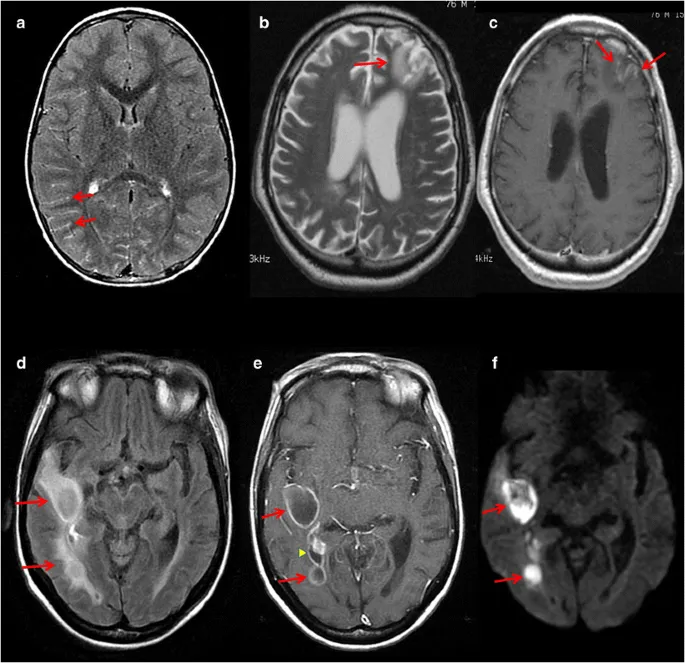

- Features: Ring enhancement, central DWI restriction, surrounding vasogenic edema.

- Subdural/Epidural collections, often crescentic or lentiform.

- Shows DWI restriction.

- Ventriculitis:

- Ependymal enhancement.

- Intraventricular debris/pus with DWI restriction.

- Imaging: Multiple (often <10) ring-enhancing lesions, typically in basal ganglia & corticomedullary junction; surrounding vasogenic edema.

- 'Asymmetric target sign' (eccentric nodule).